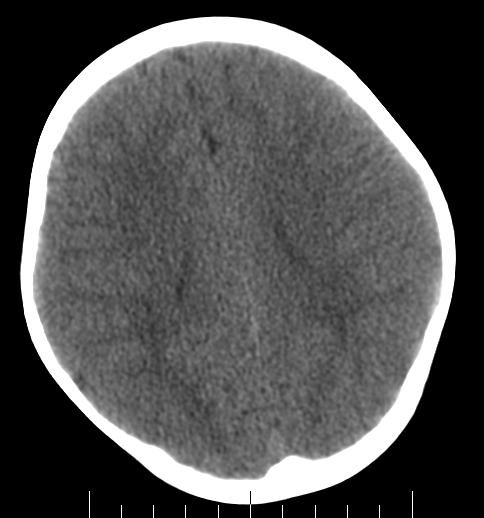

女,3岁,头部外伤一小时。半卵圆中心低密度是什么意思,病灶?侧脑室?请指教。

正常表现

脑白质

幼儿正常脑白质表现,长期观察,必要时mr

从层面看不是侧脑室,考虑低密度变,建议mri。

不是侧脑室,考虑正常脑白质。为慎重,建议mr!